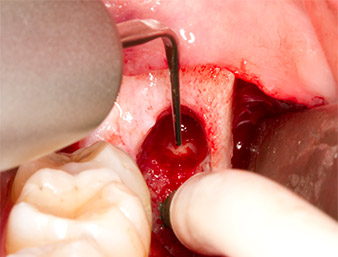

After block and local anaesthesia, the operating site was opened up and the soft tissue exposed for buccal retromolar access (Fig. 3).

sulcular incision

Fig. 3: The sulcular incision begins in mid-tooth 36 (LL6), with distal extension on the ascending ramus.

The tissue above the root remnant was not completely ossified and consisted for the most part of granulation tissue modified by inflammation (Fig. 4).

Granulation tissue

Fig. 4: Two Langenbeck retractors and a raspatorium expose the operating area. Granulation tissue of the incompletely healed first osteotomy can be seen.